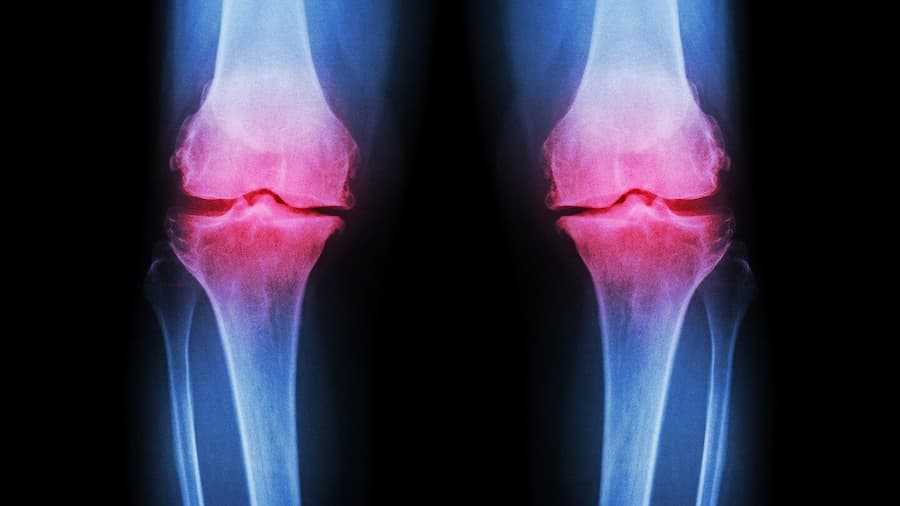

Как справиться с ревматоидным артритом колена когда лекарства не помогают?

Всемирная организация здравоохранения называет ревматоидный артрит коленного сустава одной из самых распространенных патологий опорно-двигательного аппарата, а не допустить усугубления данной болезни помогут медицинские ортопедические наколенники купить Киев хорошего качества. Настоящие причины возникновения недуга врачи до сих пор не установили, они лишь называют провоцирующие факторы, в числе которых инфекционное воспаление.

Это заболевание резко снижает качество жизни, поскольку постепенно происходит поражение всех суставов организма, но в самом начале начинают страдать именно колени. Имунная система человека атакует собственный организм, изначальнопоражая хрящевые ткани. Начните как можно раньше комплексное лечение болезни без лекарств, не забывая наколенники при ревматоидном артрите купить Киев из эластичной ткани.